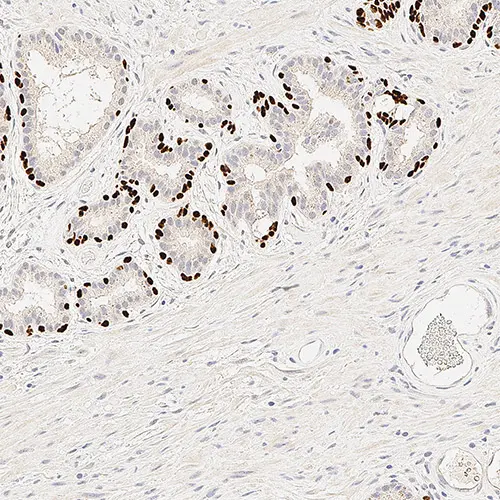

Human prostate: immunohistochemical staining for p63. p63: clone 7JUL

p63 is a nuclear transcription factor, reported to be expressed in a number of normal tissues including proliferating cells of the epithelium, cervix, urothelium and prostate. p63 is also reported to be expressed in most poorly differentiated squamous cell carcinomas.